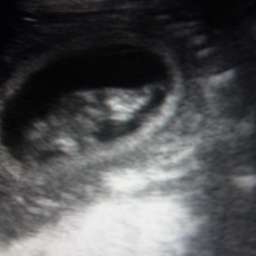

9.4.2015, 32.Tag: "Lieber Fiete! Ich habe gute Nachrichten für Dich: Du wirst Vater. Unser Date blieb nicht ohne Folgen.

5 kleine gesunde Wunder mit pochenden Herzen haben wir im Ultraschall gesehen. Freust Du Dich? Deine Adele"

Adeles Bauchumfang ist aktuell 45cm. Also 3cm Wachstum in 4 Tagen. Gewicht: 6,6Kilo. Oho, jetzt geht es los...!!!

Adeles Wunder

Adele hat den Ultraschall übrigens super gemeistert. Kahlrasur am Bauch hat sie abgelehnt. Aber ansonsten war sie ziemlich entspannt und in Vorfreude auf ihre Fleischwurst.